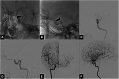

Case presentation: A 60-year-old woman with chronic hypertension rapidly developed right hemiplegia. She had been suffering from slight headache and abnormal sensation in the right limbs 1 week before the ictus. MRI demonstrated small acute infarctions in the left middle cerebral artery (MCA) territory. The left ICA was not visualized on MRA. Diffusion-perfusion mismatch was indicated by the automated image postprocessing system. Endovascular recanalization was planned to prevent the progression of cerebral infarction. After advancing a 5MAX ACE, initial left ICA angiography was performed, resulting in extravasation of contrast medium from the C2 segment of the left ICA. 3D rotational angiography revealed left ICA dissection of the C2 segment. To secure hemostasis, the patient underwent internal trapping at the C1 and C2 segments of the left ICA. Collateral flow to the left MCA via an anterior communicating artery was observed. On day 28, the patient was transferred to a rehabilitation hospital with right hemiplegia and motor aphasia.